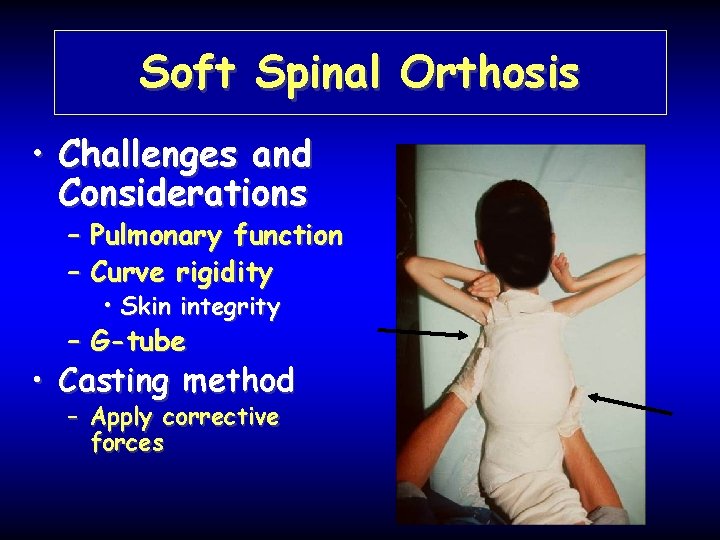

Soft Spinal Orthosis • Challenges and Considerations – Pulmonary function – Curve rigidity • Skin integrity – G-tube • Casting method – Apply corrective forces